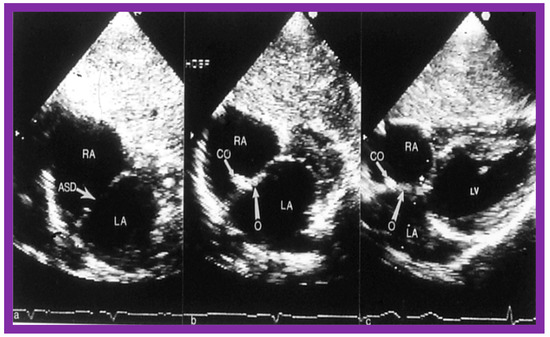

7. Balloon Sizing